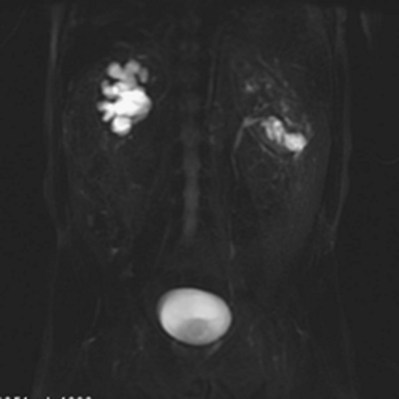

Certain terms used in this chapter as descriptors of this process need to be defined from the outset. Hydronephrosis is the dilation of the renal pelvis or calyces. It may be associated with obstruction but may be present in the absence of obstruction. Obstructive uropathy refers to the functional or anatomic obstruction of urinary flow at any level of the urinary tract. Obstructive nephropathy is present when the obstruction causes functional or anatomic renal damage.

The prevalence of urinary tract obstruction is best estimated from autopsy series. In a series of 59,064 autopsies performed on individuals ranging from neonates to geriatric subjects, hydronephrosis was reported in 3.1% (Bell, 1950). There were no gender differences in this series until the age of 20 years. However, hydronephrosis was more prevalent in women in the 20- to 60-year interval. The latter was attributed to pregnancy and development of gynecologic malignancies. It was more prevalent in males after age 60 years, because of prostatic diseases. Hydronephrosis has been reported to be present in 2% to 2.5% of children subjected to autopsy (Campbell, 1970; Tan et al, 1994). It is somewhat more prevalent in boys, and the majority of cases were in subjects younger than 1 year. The aforementioned prevalences are most likely an underestimate of obstructive events, because temporary bouts of obstruction such as those induced by prior pregnancy or stone episodes were not captured.

Compensatory renal growth (CRG) of the unobstructed kidney was first described by Hinman (1943). This phenomenon has been subsequently demonstrated in a number of other animal models of UUO (Taki et al, 1983; Peters et al, 1993). There is evidence that it occurs in the human fetus. An increase in contralateral renal volume has been detected ultrasonographically when contralateral hydronephrosis or unilateral renal agenesis is present (Mandell et al, 1993).

The mechanisms and nature of this growth are influenced by several factors including age, and degree and duration of obstruction. Both hyperplastic and hypertrophic CRG have been demonstrated (Dicker and Shirley, 1973; Castle and McDougal, 1984; Peters et al, 1993). CRG was demonstrated to decrease progressively with increasing age at which the obstruction occurred in animal models (Taki et al, 1983). Studies of humans subjected to nephrectomy, a functional surrogate for obstruction, have demonstrated that a reduction in CRG occurs with increasing age (Edgren et al, 1976). Animal experiments have also demonstrated that compensatory growth is directly proportional to the duration of obstruction (Chevalier et al, 1999). Compensatory growth is less prominent with partial than with total UUO (Chevalier and Kaiser, 1984; Eskild-Jensen et al, 2001). While the kidney enlarges, an increase in the number of nephrons or glomeruli does not occur (Peters et al, 1993). However, an increase in the length of the proximal tubule has been described, which may be due to an increase in cell size (Moller, 1988). In addition, there is augmented extracellular matrix synthesis and growth of mesangial cells (Kasinath et al, 2006; Sinuani et al, 2006). Insulin-like growth factor I (IGF-I), a mitogenic and anabolic peptide, may play a role in compensatory renal growth after obstruction. There is both animal and clinical evidence for its role. In rats, mean renal IGF-I is significantly elevated in the normal kidney compared with the contralateral 7-day obstructed kidney (Serel et al, 2000). Inferences can also be made from nephrectomy performed in animals and humans. Renal IGF-I mRNA levels are increased in immature rats previously subjected to nephrectomy (Mulroney et al, 1991). Significant increases in serum IGF-I have been demonstrated in humans after donor nephrectomy and peak 6 months after the procedure. Serum IGF-I was positively correlated with increases in renal volume demonstrated on serial postoperative imaging (Nam and Chang, 1999). It has also been demonstrated that the expression of IGF-I may be age dependent. Although renal IGF-I mRNA levels were found to be elevated after nephrectomy in immature rats, this did not occur in adult rats (Mulroney et al, 1991). Exogenous IGF-1 can attenuate renal injury from obstruction (Chevalier et al, 2000). Other growth factors, cytokines, and enzymes may be involved in regulating CRG, including IGF binding protein–3 (IGFBP-3), vascular endothelial growth factor (VEGF), matrix metalloproteinase–9 (MMP-9), interleukin-10 (IL-10), and TGF-β (Yildiz et al, 2008). Experimental studies suggest that CRG may be influenced by mitochondrial respiration (Tucci et al, 2008). The presence of compensatory growth in infants has been considered by some as an indicator that contralateral hydronephrosis is functionally significant (Koff and Peller, 1995). However, this approach has been challenged by others (Brandel et al, 1996). In addition, it was demonstrated that functional deterioration occurred in a rat model of partial UUO before compensatory growth developed in the contralateral renal unit. This implies that there may be a risk for functional renal loss if one uses only compensatory growth as an indication of correction of obstruction (Wen et al, 1999). Studies in children with unilateral renal tumors have shown that partial nephrectomy is associated with a greater degree of CRG versus nephrectomy, as assessed by ultrasonography (US) (Cozzi et al, 2007). The cause for this differential response is unknown but may be due the generation of more CRG factors in this setting.